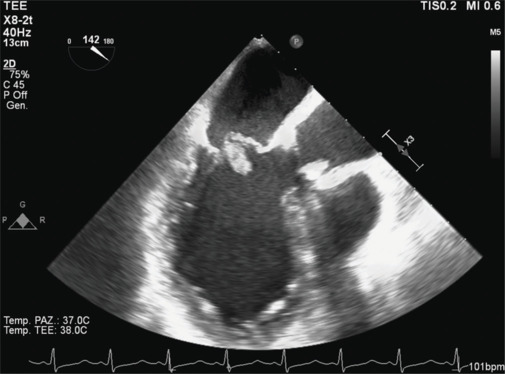

Papillary muscle rupture (PMR) is a cardiac surgical emergency, and early treatment is associated with better short- and long-term survival outcomes. The sensitivity of the transthoracic echocardiogram for PMR is rather low (65%), and in acute, the diagnosis could be difficult given the clinical, laboratory, and radiological aspects not specific for the disease. We report a case of incomplete anterolateral PMR in a patient admitted to intensive care with bilateral pneumonia and septic shock. Transesophageal echocardiogram was fundamental for a better visualization of mitral subvalvular apparatus, allowing a correct diagnosis and a tempestive treatment.

乳头状肌破裂(PMR)是一种心脏外科急诊,早期治疗与较好的短期和长期生存结果相关。经胸超声心动图对PMR的敏感性相当低(65%),在急性期,由于临床、实验室和放射学方面的原因,诊断可能很困难。我们报告一例不完全前外侧PMR患者入院重症监护双侧肺炎和感染性休克。经食管超声心动图是更好地显示二尖瓣下器官的基础,允许正确的诊断和快速治疗。